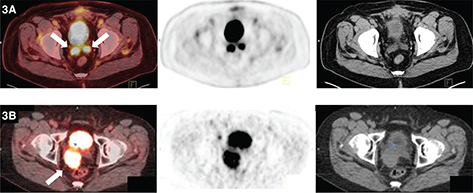

Fig 4

Figure 4. Lymph nodes. FDG PET/CT demonstrates hypermetabolic activity within left supraclavicular (thick solid arrow) and periaortic lymph nodes (thick open arrow). This patient was undergoing restaging for a history of seminoma. Findings on PET/CT were consistent with retroperitoneal and left supraclavicular nodal disease.